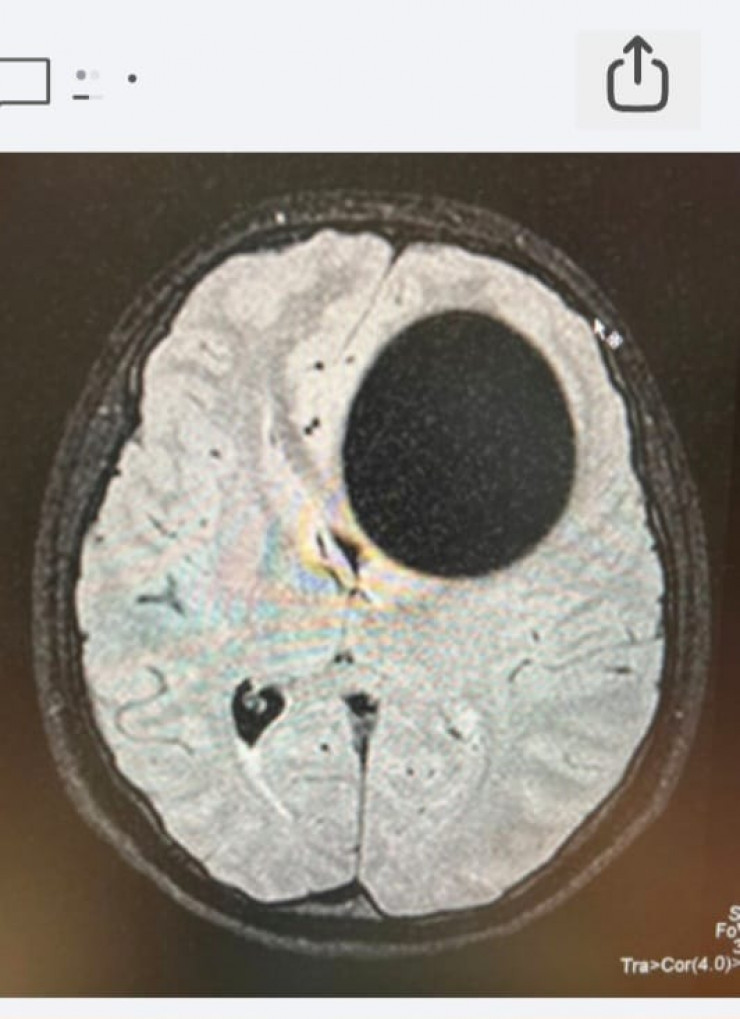

КТ-снимок до операции.

КТ-снимок после операции. Материал предоставлен общественным объединением KAZNEURO